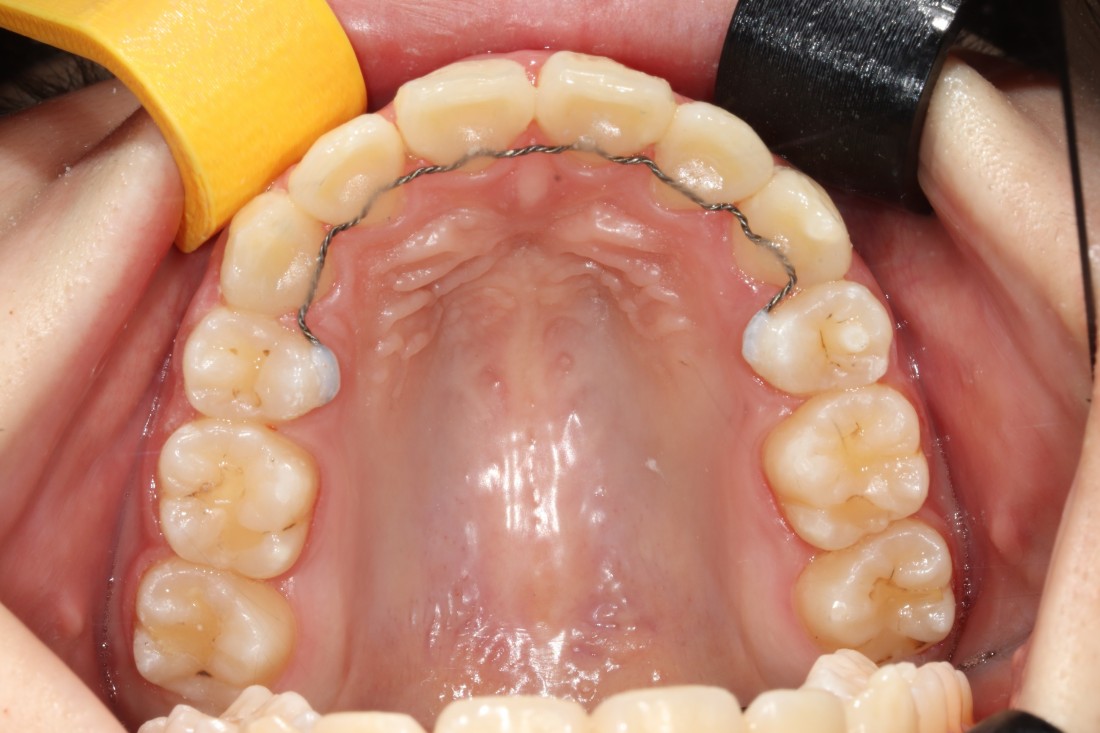

때로는 치아교정만으로 해결하는 것 보다

임플란트 식립을 동시에 해서

더욱 최상의 치료결과를 얻을 수 있을 때가

생기는데요.

20년 경력의 교정전문의 진료와 함께

구강외과 전문의 대표원장님의

협진도 동시에 진행하여

치아교정 기간을 단축하고

성공적으로 고른 치열을 완성하였습니다.